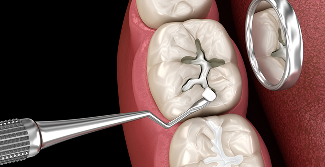

레진 충전

치아와 유사한 색상의 복합레진을 이용해 충치나 손상된 부위를 메우며

심미성이 뛰어나고 앞니나 작은 충치 치료에 적합합니다.

• 간단한 치료

• 합리적인 비용